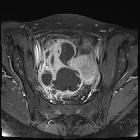

MRI

Can be useful especially when sonography is inconclusive or if the gas content is difficult to be differentiated from bowel gas .

Typically seen as thick-walled fluid-filled pelvic mass(es)

- T1: abscess contents typically hypointense

- T2: abscess contents typically heterogeneous signal or hyper-intense